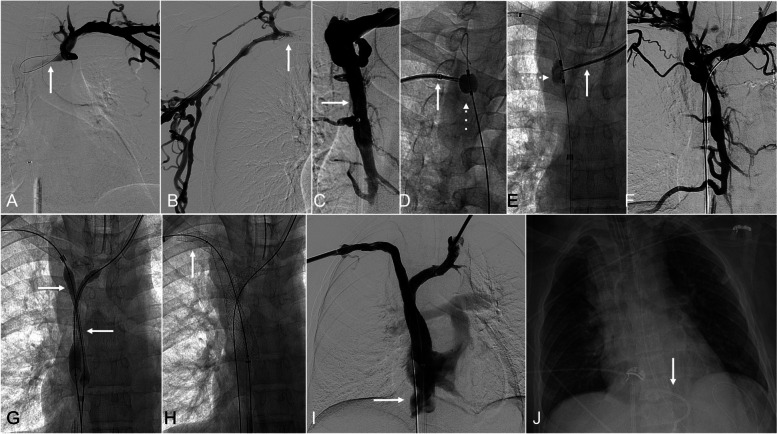

Purpose: Endovascular recanalization and stent reconstruction constitute an effective and safe treatment option for symptomatic thoracic central venous obstruction (TCVO). Rare life-threatening adverse events are possible during or immediately following the procedure, with the most feared one being hemopericardium with cardiac tamponade. A technique to improve efficiency in detection and treatment of cardiac tamponade is described.

Materials and methods: An institutional protocol was established for intraprocedural transthoracic echocardiographic monitoring during the TCVO recanalization procedures. The lower chest and upper abdomen were prepared within the sterile field. A separate stand was set up with unopened supplies needed for pericardial drain placement. Intermittent echocardiographic monitoring was performed throughout the TCVO procedure using a dedicated curvilinear probe prepared on the field. If indicated, an image guided pericardial drain was placed expeditiously.

Results: Four cases of cardiac tamponade were encountered during or immediately post-procedure. All cases demonstrated technically successful and prompt pericardial drain placement with immediate reversal of the tamponade physiology.

Conclusion: Echocardiographic monitoring during TCVO reconstruction by interventional radiologists is a useful technique which may aid in early diagnosis and management of cardiac tamponade.